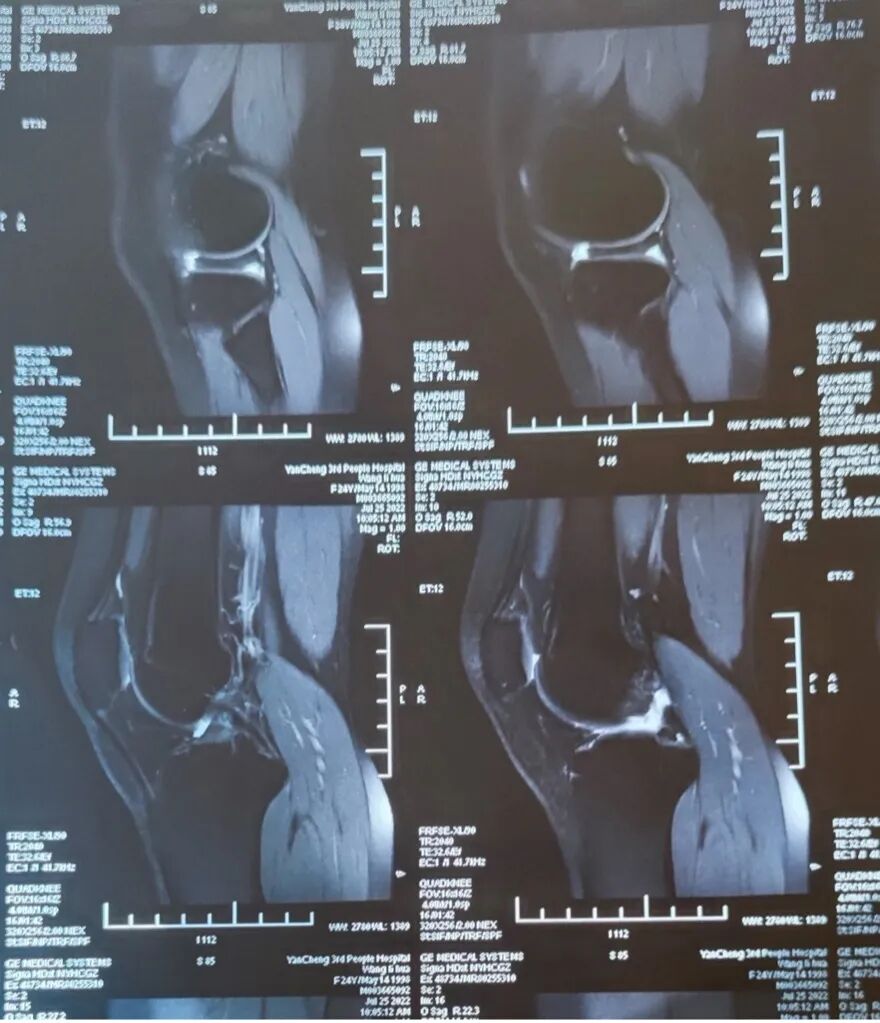

暑假后疼痛再次袭来,我知道不得不去医院了。心里的不安被证实,核磁共振显示盘状半月板,有撕裂,需要手术。

术前磁共振检查丨作者供图

到底是不是盘状半月板,查个磁共振就很清楚了,磁共振上可以很明显地看出半月板是否为盘状、有无撕裂等情况。